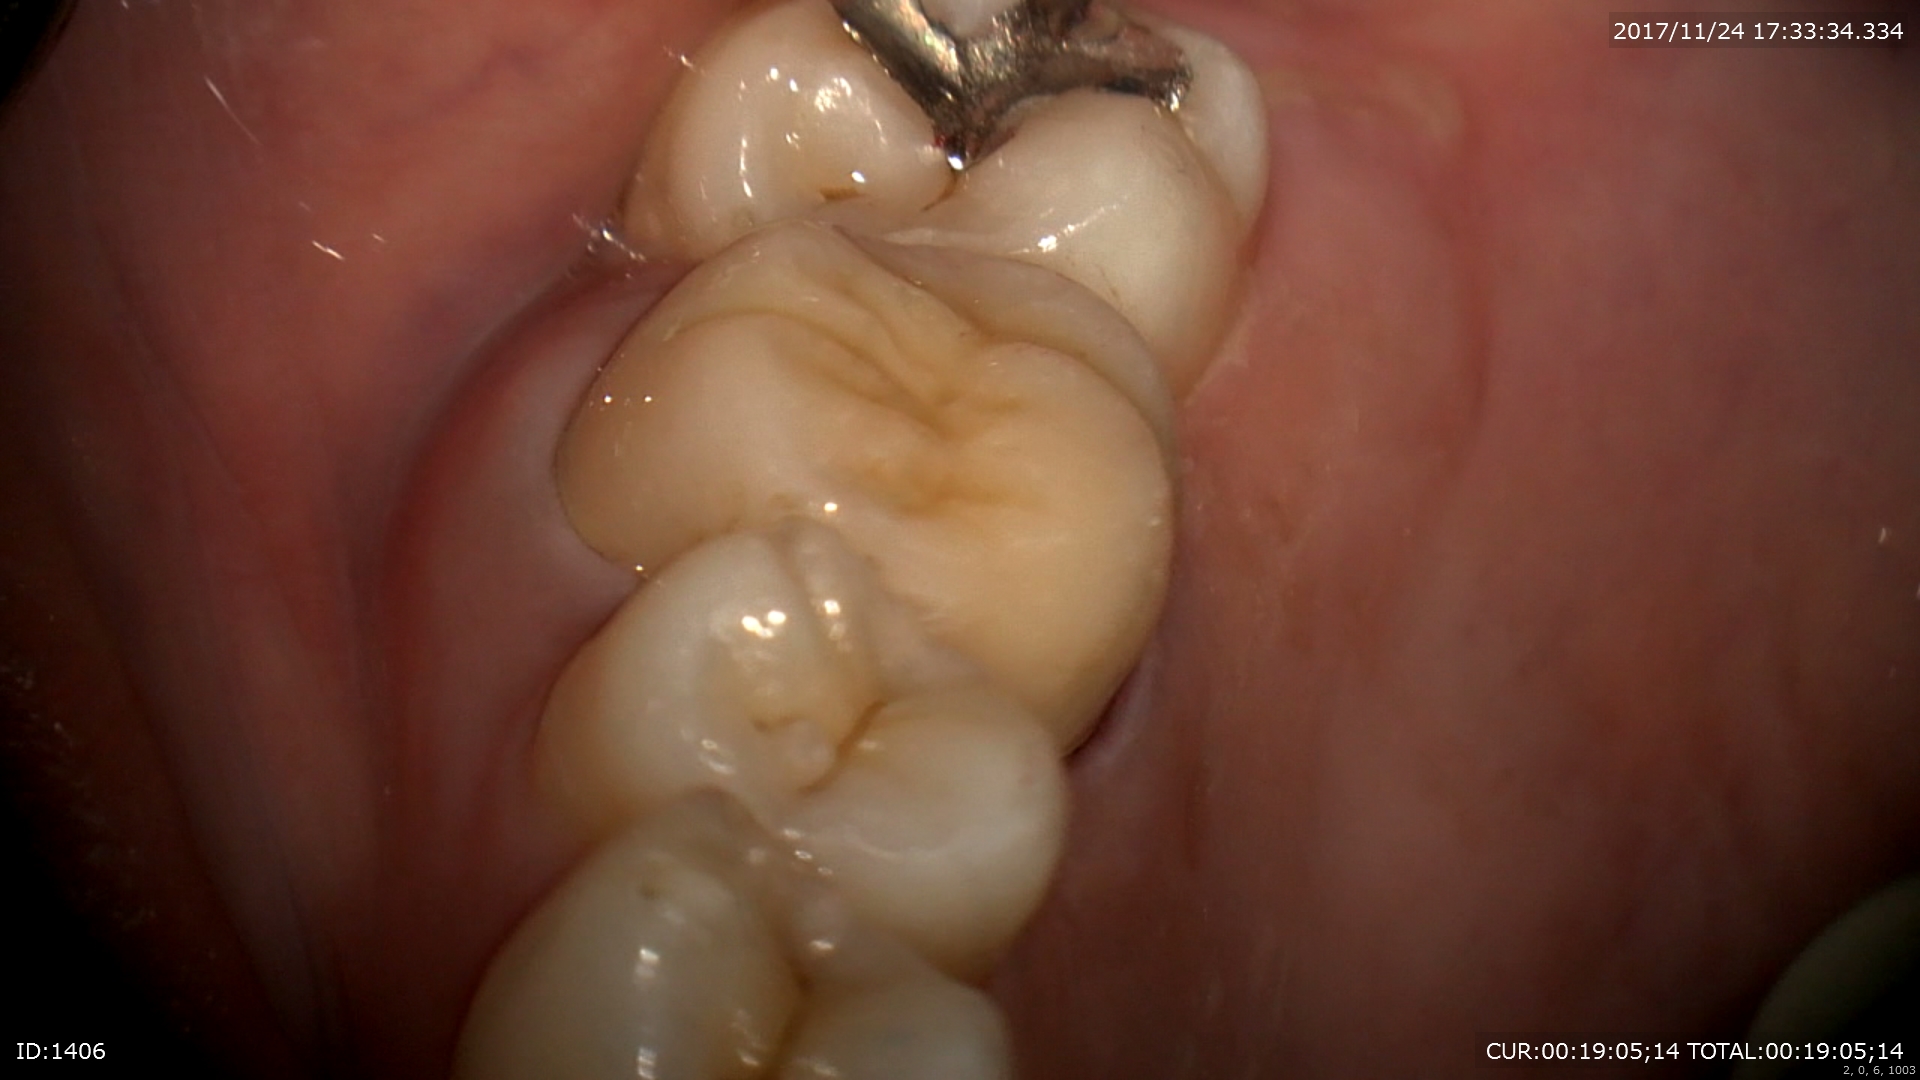

装着

術前右 術後左 金属を使わない治療は体に良いですね。